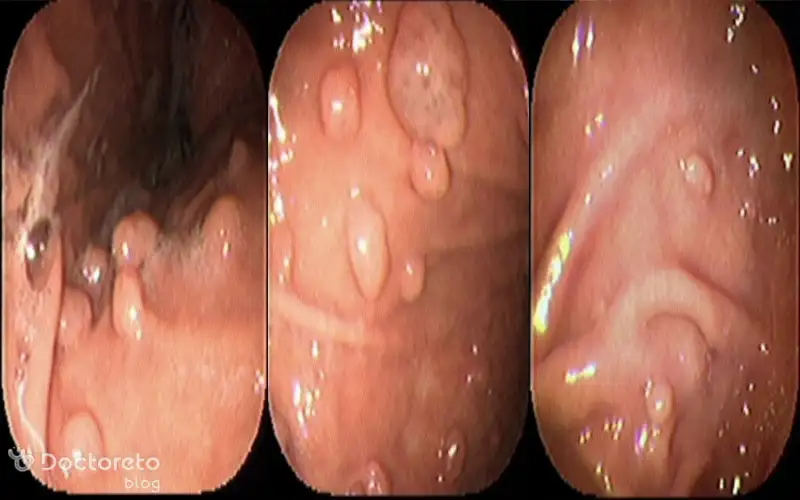

عکس پولیپ های خوش خیم معده

پولیپهای معده در کنار شایع بودن، اغلب خوشخیم هستند. اما باید توجه داشت که برخی از آنها ممکن است پتانسیل تبدیل به یک ضایعه بدخیم را داشته باشند؛ بنابراین مشاهده و ارزیابی دقیق نوع این پولیپها مهم است. اغلب این پولیپها بدون علامت بوده و در حین اندوسکوپی تصادفی کشف میشوند. شناسایی و پایش آنها اهمیت دارد تا در صورت تغییر شکل یا اندازه، اقدامات پیشگیرانه انجام شود.